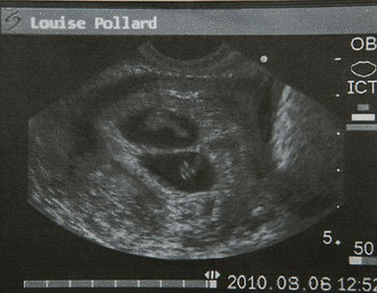

波拉德表示,她是本月6日在英國(guó)曼徹斯特一家私人診所做的超聲波檢查,影像資料顯示,她已經(jīng)成功受孕8周而且懷的是雙胞胎。自今年6月上旬波拉德公開(kāi)承認(rèn)已答應(yīng)為奧馬爾夫婦代孕以來(lái),她一直是英國(guó)媒體關(guān)注的焦點(diǎn)之一。

2010年8月6日,超聲波檢查顯示波拉德懷的是雙胞胎。